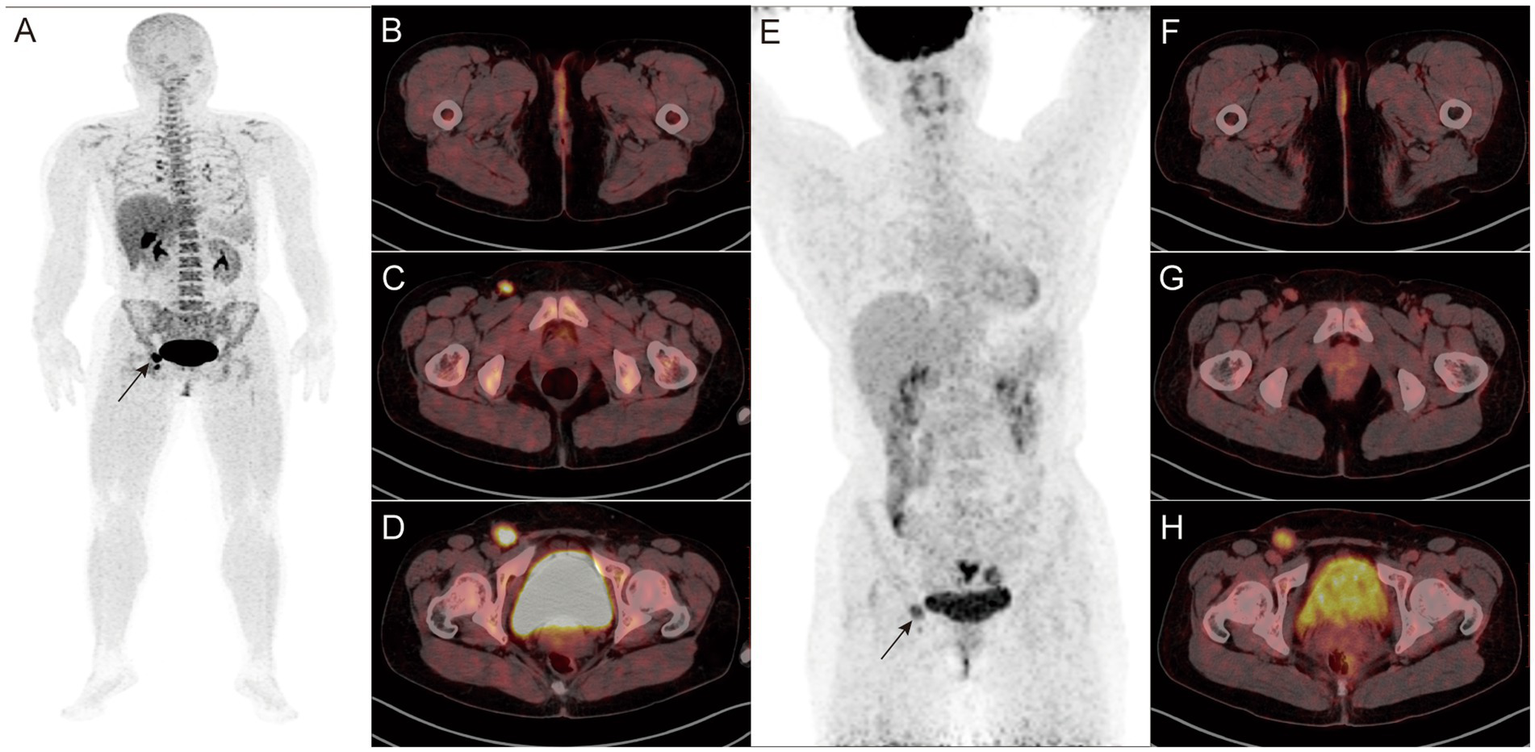

18F-P3BZA PET/CT detected primary lesions in all newly diagnosed patients (100%, 12/12). The SUVmax of 12 primary tumors was 9.5 ± 9.1, with 10 cases of cutaneous melanoma having an SUVmax of 5.6 ± 3.3 (Figures 1A–D) and 2 cases of ocular melanoma having an SUVmax of 33.4 and 16.8 (Figures 1E–H). No abnormalities were observed at the surgical site in seven postoperative follow-up patients.

Figure 1

(A–D) Findings in a 68-year-old female patient diagnosed with melanoma more than 20 days before the start of the study. 18F-P3BZA PET/CT MIP (maximum intensity projection) (A) showing a radioactive accumulation shadow on the outer side of the right thigh, and CT (B), PET (C), and PET/CT (D) showing local skin thickening on the outer side of the right thigh with increased radioactive uptake (SUVmax: 8.8). (E–H) Findings in a 39-year-old female patient diagnosed with melanoma 1 week before the study. 18F-P3BZA PET/CT MIP (E) showing a radioactive accumulation shadow in the right eye, and CT (F), PET (G), and PET/CT (H) showing high-density nodules on the posterior inner wall of the right eyeball, accompanied by radioactive concentration (SUVmax: 33.4).